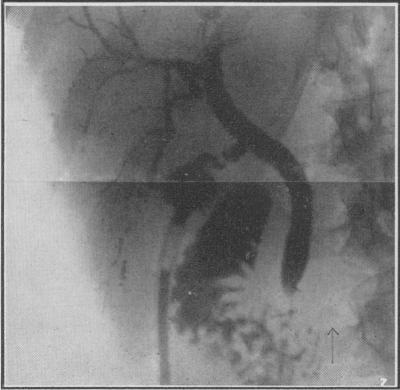

Post-Operative Perfusion of the Biliary Ductal System: (Preliminary Report).

Can Med Assoc J. 1940 Nov;43(5):411-8.